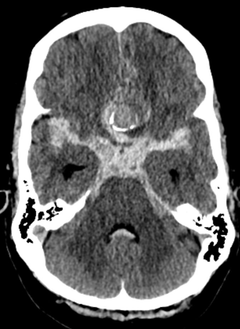

En ny studie från HUS visar att behandlingen av icke rupturerade hjärnaneurysm i Helsingfors är exceptionellt säker och effektiv i internationell jämförelse. Resultaten publicerades i den prestigefyllda tidskriften Journal of Neurosurgery.

Forskarna granskade kvaliteten på behandlingen av icke rupturerade hjärnaneurysm. Studien behandlade 169 patienter som vårdades på HUS. Patienterna genomgick antingen mikrokirurgisk (29 procent av patienterna) eller endovaskulär (71 procent) behandling av mellan december 2022 och augusti 2024.

Även om patienternas kliniska utfall var utmärkt avslöjade känsliga MR diffusionsviktade sekvenser (DWI) nya, små ischemiska förändringar, det vill säga förändringar på grund av syrebrist, hos 63 procent av patienterna. Största delen av dessa patienter var symtomfria, men de hade en förhöjd risk att få övergående neurologiska symtom. Resultatet visar att de traditionella indikatorerna för återhämtning och funktionsförmåga inte identifierar alla effekter av behandlingen på hjärnan.